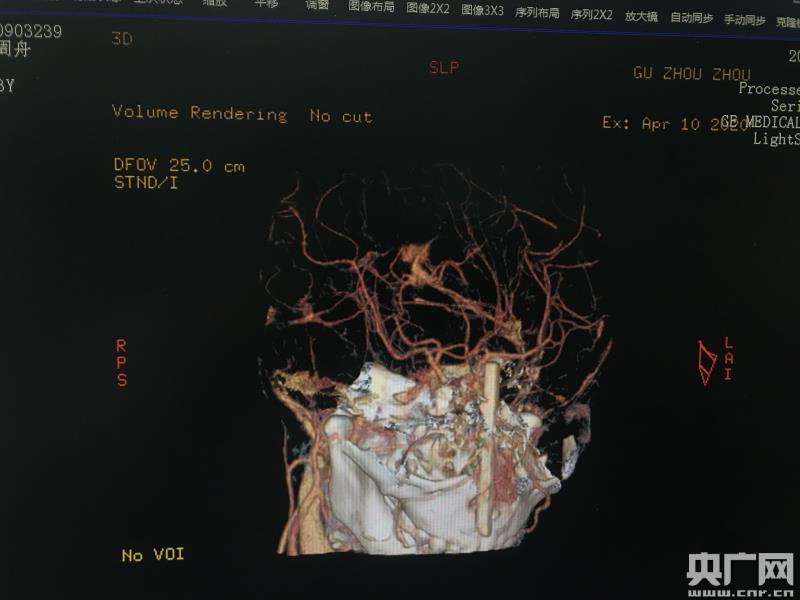

孩子家长都吓坏了,他们立刻抱起浩浩直奔当地医院,经过两次转院,由于情况紧急,还来不及等到检查报告出来,就转来上海市儿童医院,此时已是10日凌晨3点多,距离筷子插进脑部已有8小时。儿童医院神经外科、耳鼻喉头颈外科联合影像科紧急会诊。通过头部CT及CTA血管造影发现,折断的筷子已经插入浩浩颅内五厘米深,而且位置十分凶险:右侧就是眼球,左侧是大脑前动脉,四周都是重要的结构,可谓“步步惊心”。